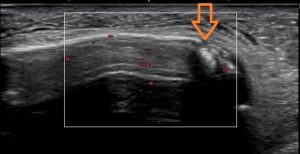

エコーで見るとこんな画像が・・・・・

矢印の先が折れている部分です。

白い線が骨です。まっすぐに線がつながってなければいけません。

しかし、矢印の先で離れてしまっているのわかりますか??

骨折と言っても、小さな骨が剥がれている感じです。